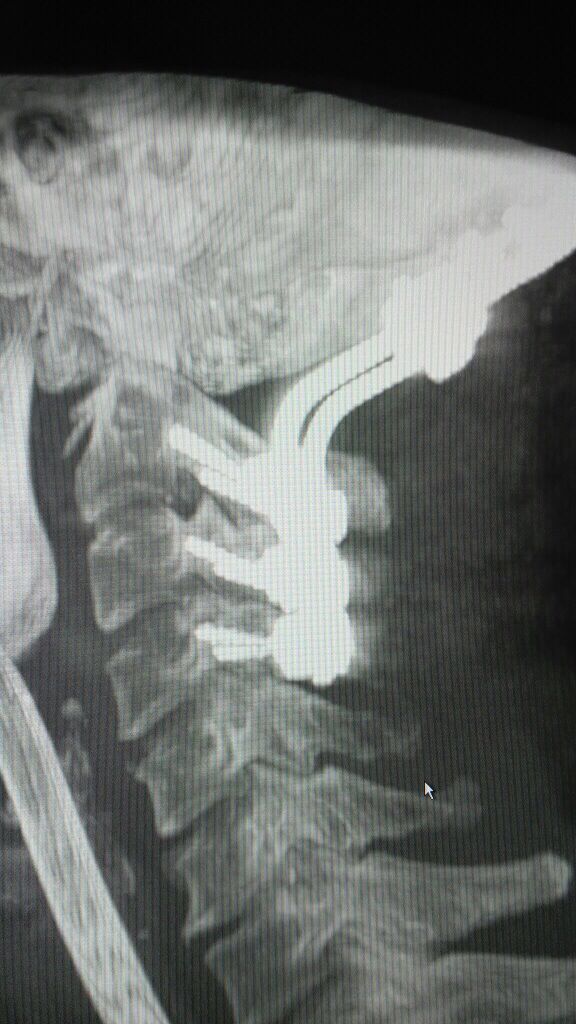

颈椎MRI,CT显示寰枢椎脱位,小脑扁桃体下疝,脊髓空洞